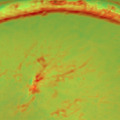

取り組みでは、Optos社の網膜画像を生成するOptosで撮影した132枚の増殖糖尿病網膜症の画像と246枚の正常眼を機械学習の一つであるディープコンボリューションニューラルネットワーク(DCNN)を用いて、未治療の増殖性糖尿病性網膜症を検出、臨床上有用な高い精度を得ることに成功した。

ディープラーニングの解析の対象にしたOptos社の広角眼底画像は、現在、健診などで主に用いられている従来型非散瞳眼底カメラの4倍以上の画角を持ち、わずか2㎜の自然瞳孔下から眼底の80%のエリアを撮影可能なため、眼科遠隔診療の革新技術と認識されている。